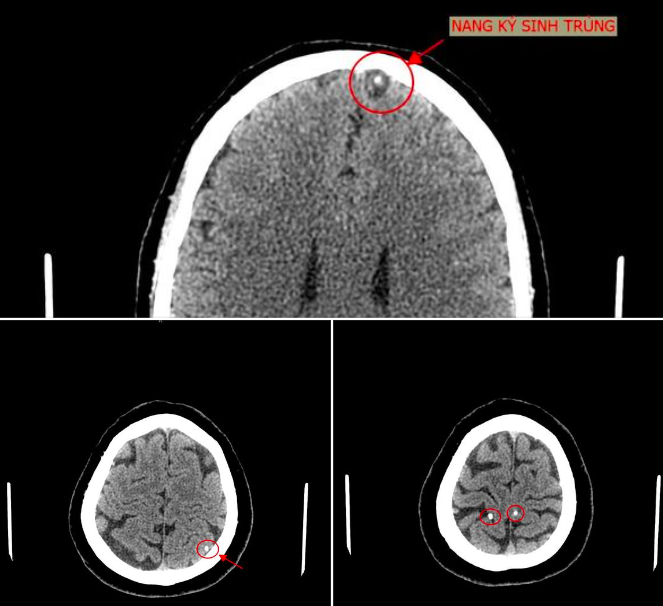

Bệnh nhân vào Trung tâm Y tế Tân Sơn (Phú Thọ) ngày 23/6. Bác sĩ khoa Chẩn đoán hình ảnh kết luận trong sọ não bệnh nhân có hình ảnh nang ký sinh trùng (ấu trùng sán não). Bệnh nhân cho biết bản thân có thói quen ăn đồ sống như gỏi cá.

Bệnh kén sán não là bệnh lý thuộc nhóm nhiễm trùng hệ thần kinh trung hương, có mức độ nguy hiểm rất cao, biểu hiện ban đầu là nhức đầu liên tục, nhức cả vùng đầu và có tính chất lan sang nhiều vùng khác.

Nghiêm trọng hơn, bệnh nhân có thể gặp phải những cơn động kinh nặng nhẹ khác nhau.